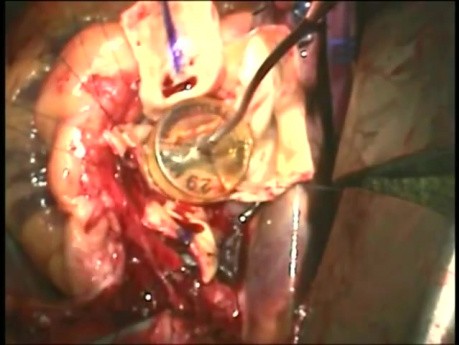

Wymiana zastawki aortalnej 2 - technika operacyjna

Dwoma głównymi powodami wymiany zastawki aortalnej są jej stenoza lub niedomykalność. Podczas zabiegu usuwa się zniszczoną zastawkę i zastępuje sztuczną - mechaniczną lub biologiczną. Zabieg zwykle wykonuje...

Wymiana zastawki aortalnej - technika operacyjna

Dwoma głównymi powoda i wymiany zastawki aortalnej są jej zwężenie lub niedomykalność. Podczas zabiegu uszkodzona zastawka jest zastępowana sztuczną - mechaniczną lub biologiczną. Zwykle zabieg wykonuje...